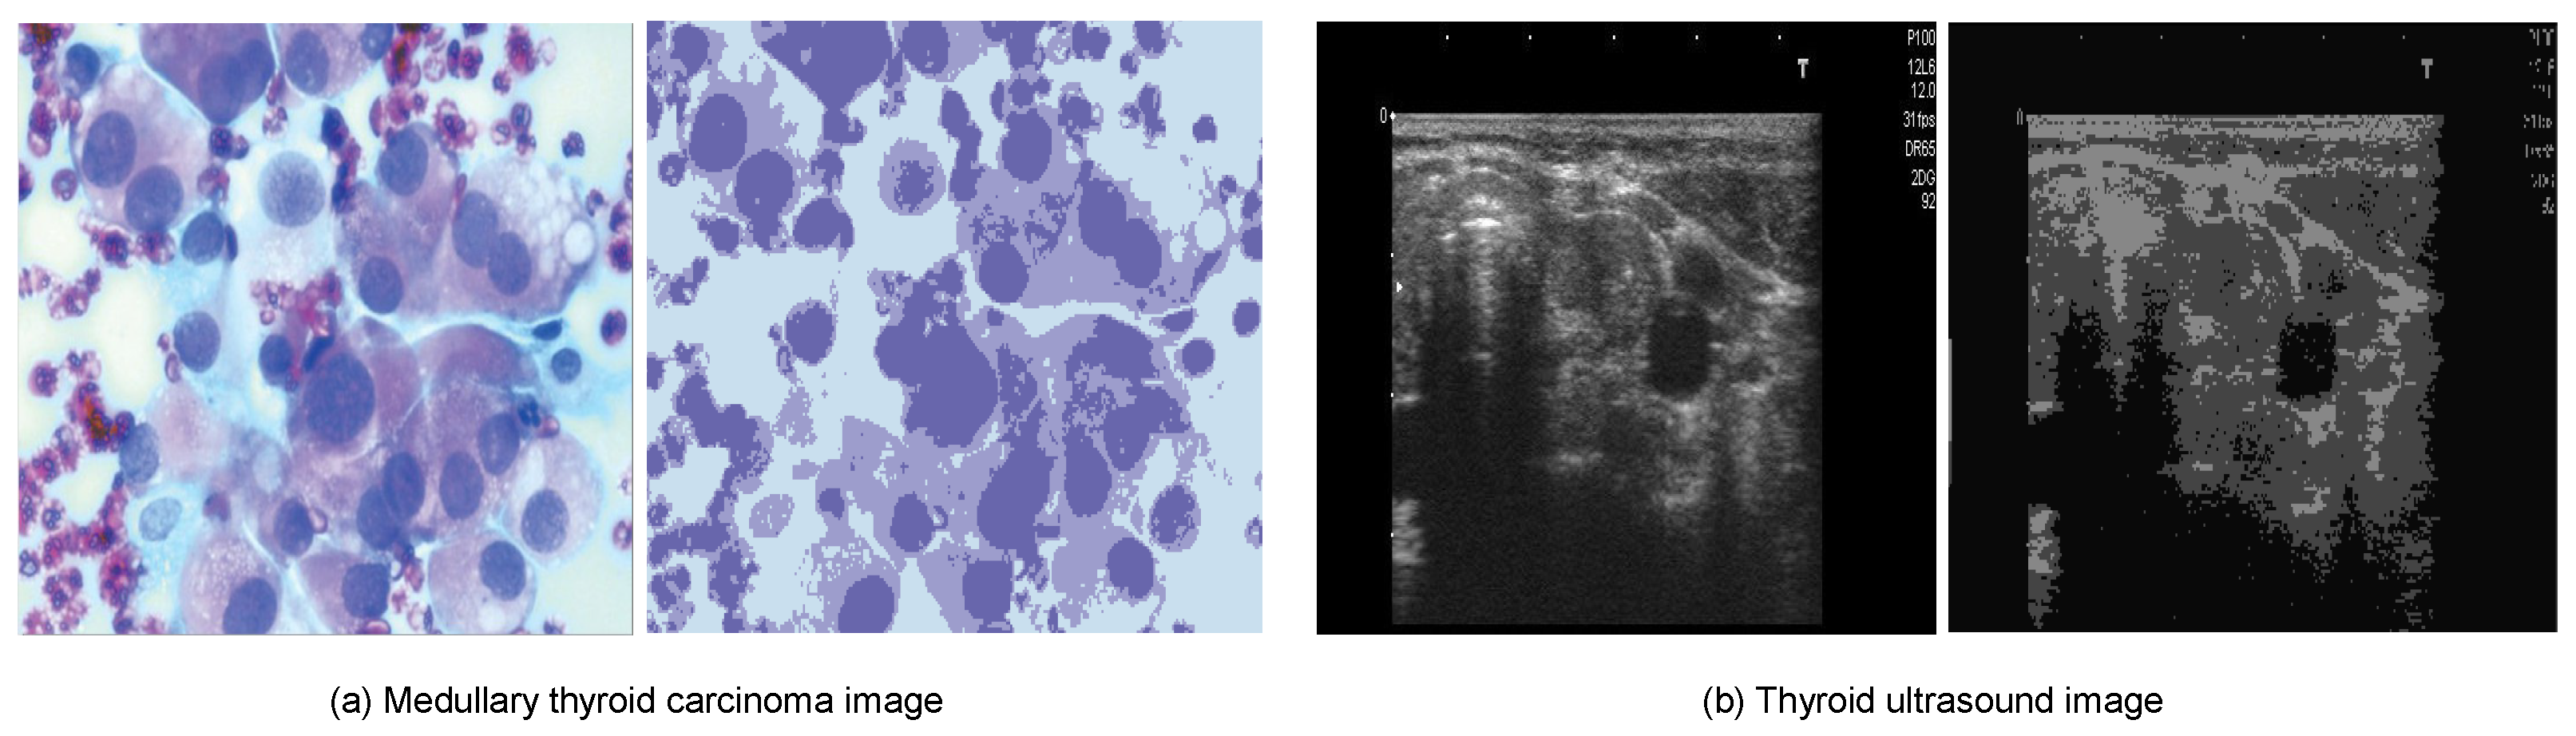

- Digital Database Thyroid Image (DDTI): The DDTI dataset serves as a valuable resource for researchers and new radiologists looking to develop algorithm-based CAD systems for thyroid nodule analysis. The dataset comprises 99 cases and 134 images, with each patient’s data stored in an XML file format [184]. Figure 4 provides an illustration of six samples from each of the thyroid carcinoma tissue types in the DDTI dataset.